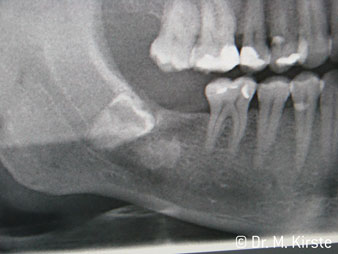

Die Winkelwahl des 45° Handstücks bringt viele Vorteile in der Anwendung. Chirurgisch tätige Kollegen, und für diese ist das Handstück in erster Linie entwickelt worden, werden schnell bemerken, dass man sehr gezielt arbeiten kann. Insbesondere bei der Weisheitszahnentfernung (Abb. 2) bedarf es keiner großen Weichteilabspreizungen im Wangenbereich (Abb. 3). Die Handstückkopfgestaltung kombiniert mit leichten Kopfdrehungen bei der Präparation lassen ein sicheres und schnelles Arbeiten im retromolaren Bereich zu.

Abb. 2